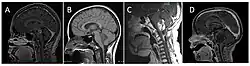

Classification of brainstem gliomas by MRI appearance.

In children, brainsteam gliomas are classified as either diffuse intrinsic pontine gliomas (DIPGs) or as focal brain stem gliomas. The latter type are less aggressive and easier to treat.[3]

The prognosis for children depends on the tumor type; most children with DIPGs live less than 18 months whereas the survival time for most children with focal gliomas is more than 18 months.[3]